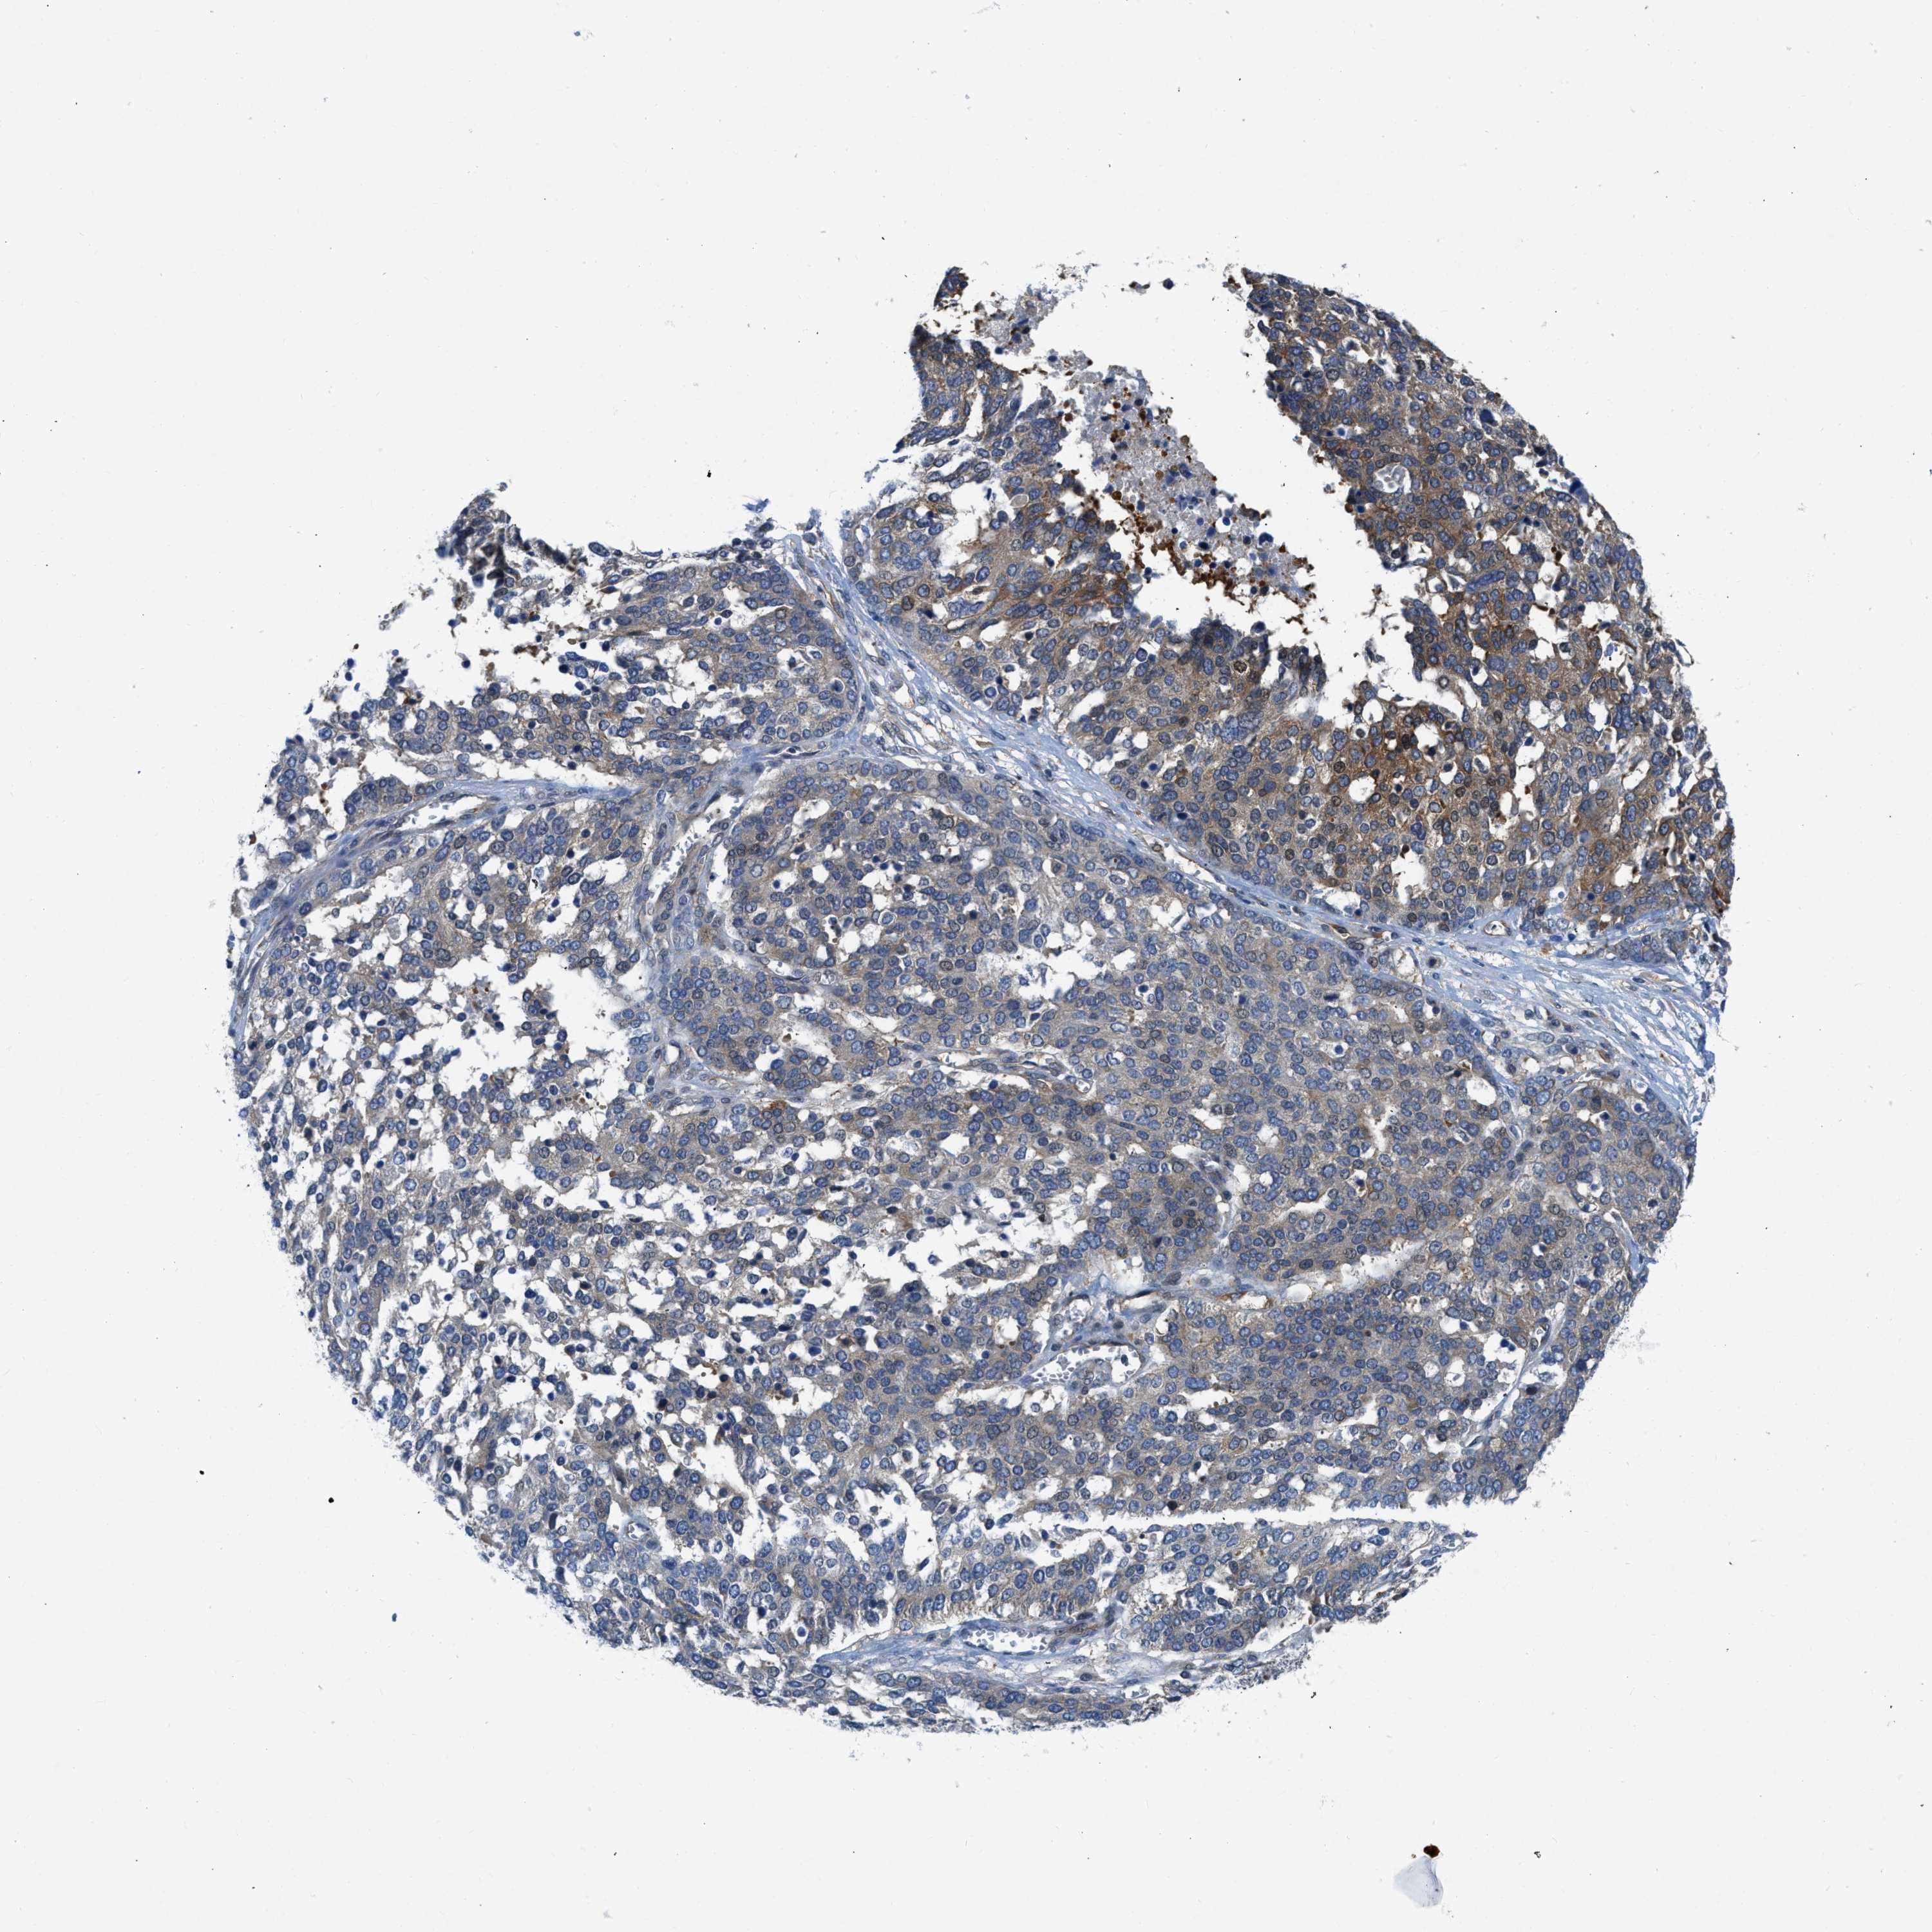

OVARIAN CANCER - Protein expressioni

A mouse-over function shows sample information and annotation data. Click on an image to view it in a full screen mode. Samples can be filtered based on level of antibody staining by selecting one or several of the following categories: high, medium, low and not detected. The assay and annotation is described here.

Note that samples used for immunohistochemistry by the Human Protein Atlas do not correspond to samples in the TCGA dataset.

Antibody stainingi

Antibody staining in the annotated cell types in the current human tissue is reported as not detected, low, medium, or high, based on conventional immunohistochemistry profiling in selected tissues. This score is based on the combination of the staining intensity and fraction of stained cells.

Each image is clickable and will lead to virtual microscopy that enables deeper exploration of all samples and also displays staining intensity scores, fraction scores and subcellular localization as well as patient and tissue information for each sample.

Antibody HPA018257

Staining

High

Medium

Low

Not detected

Intensity

Strong

Moderate

Weak

Negative

Quantity

>75%

75%-25%

<25%

None

Location

Nuclear

Cytoplasmic/membranous

Cytoplasmic/membranous,nuclear

Cystadenocarcinoma, serous, NOS

Carcinoma, endometroid

Cystadenocarcinoma, mucinous, NOS

Carcinoma, NOS